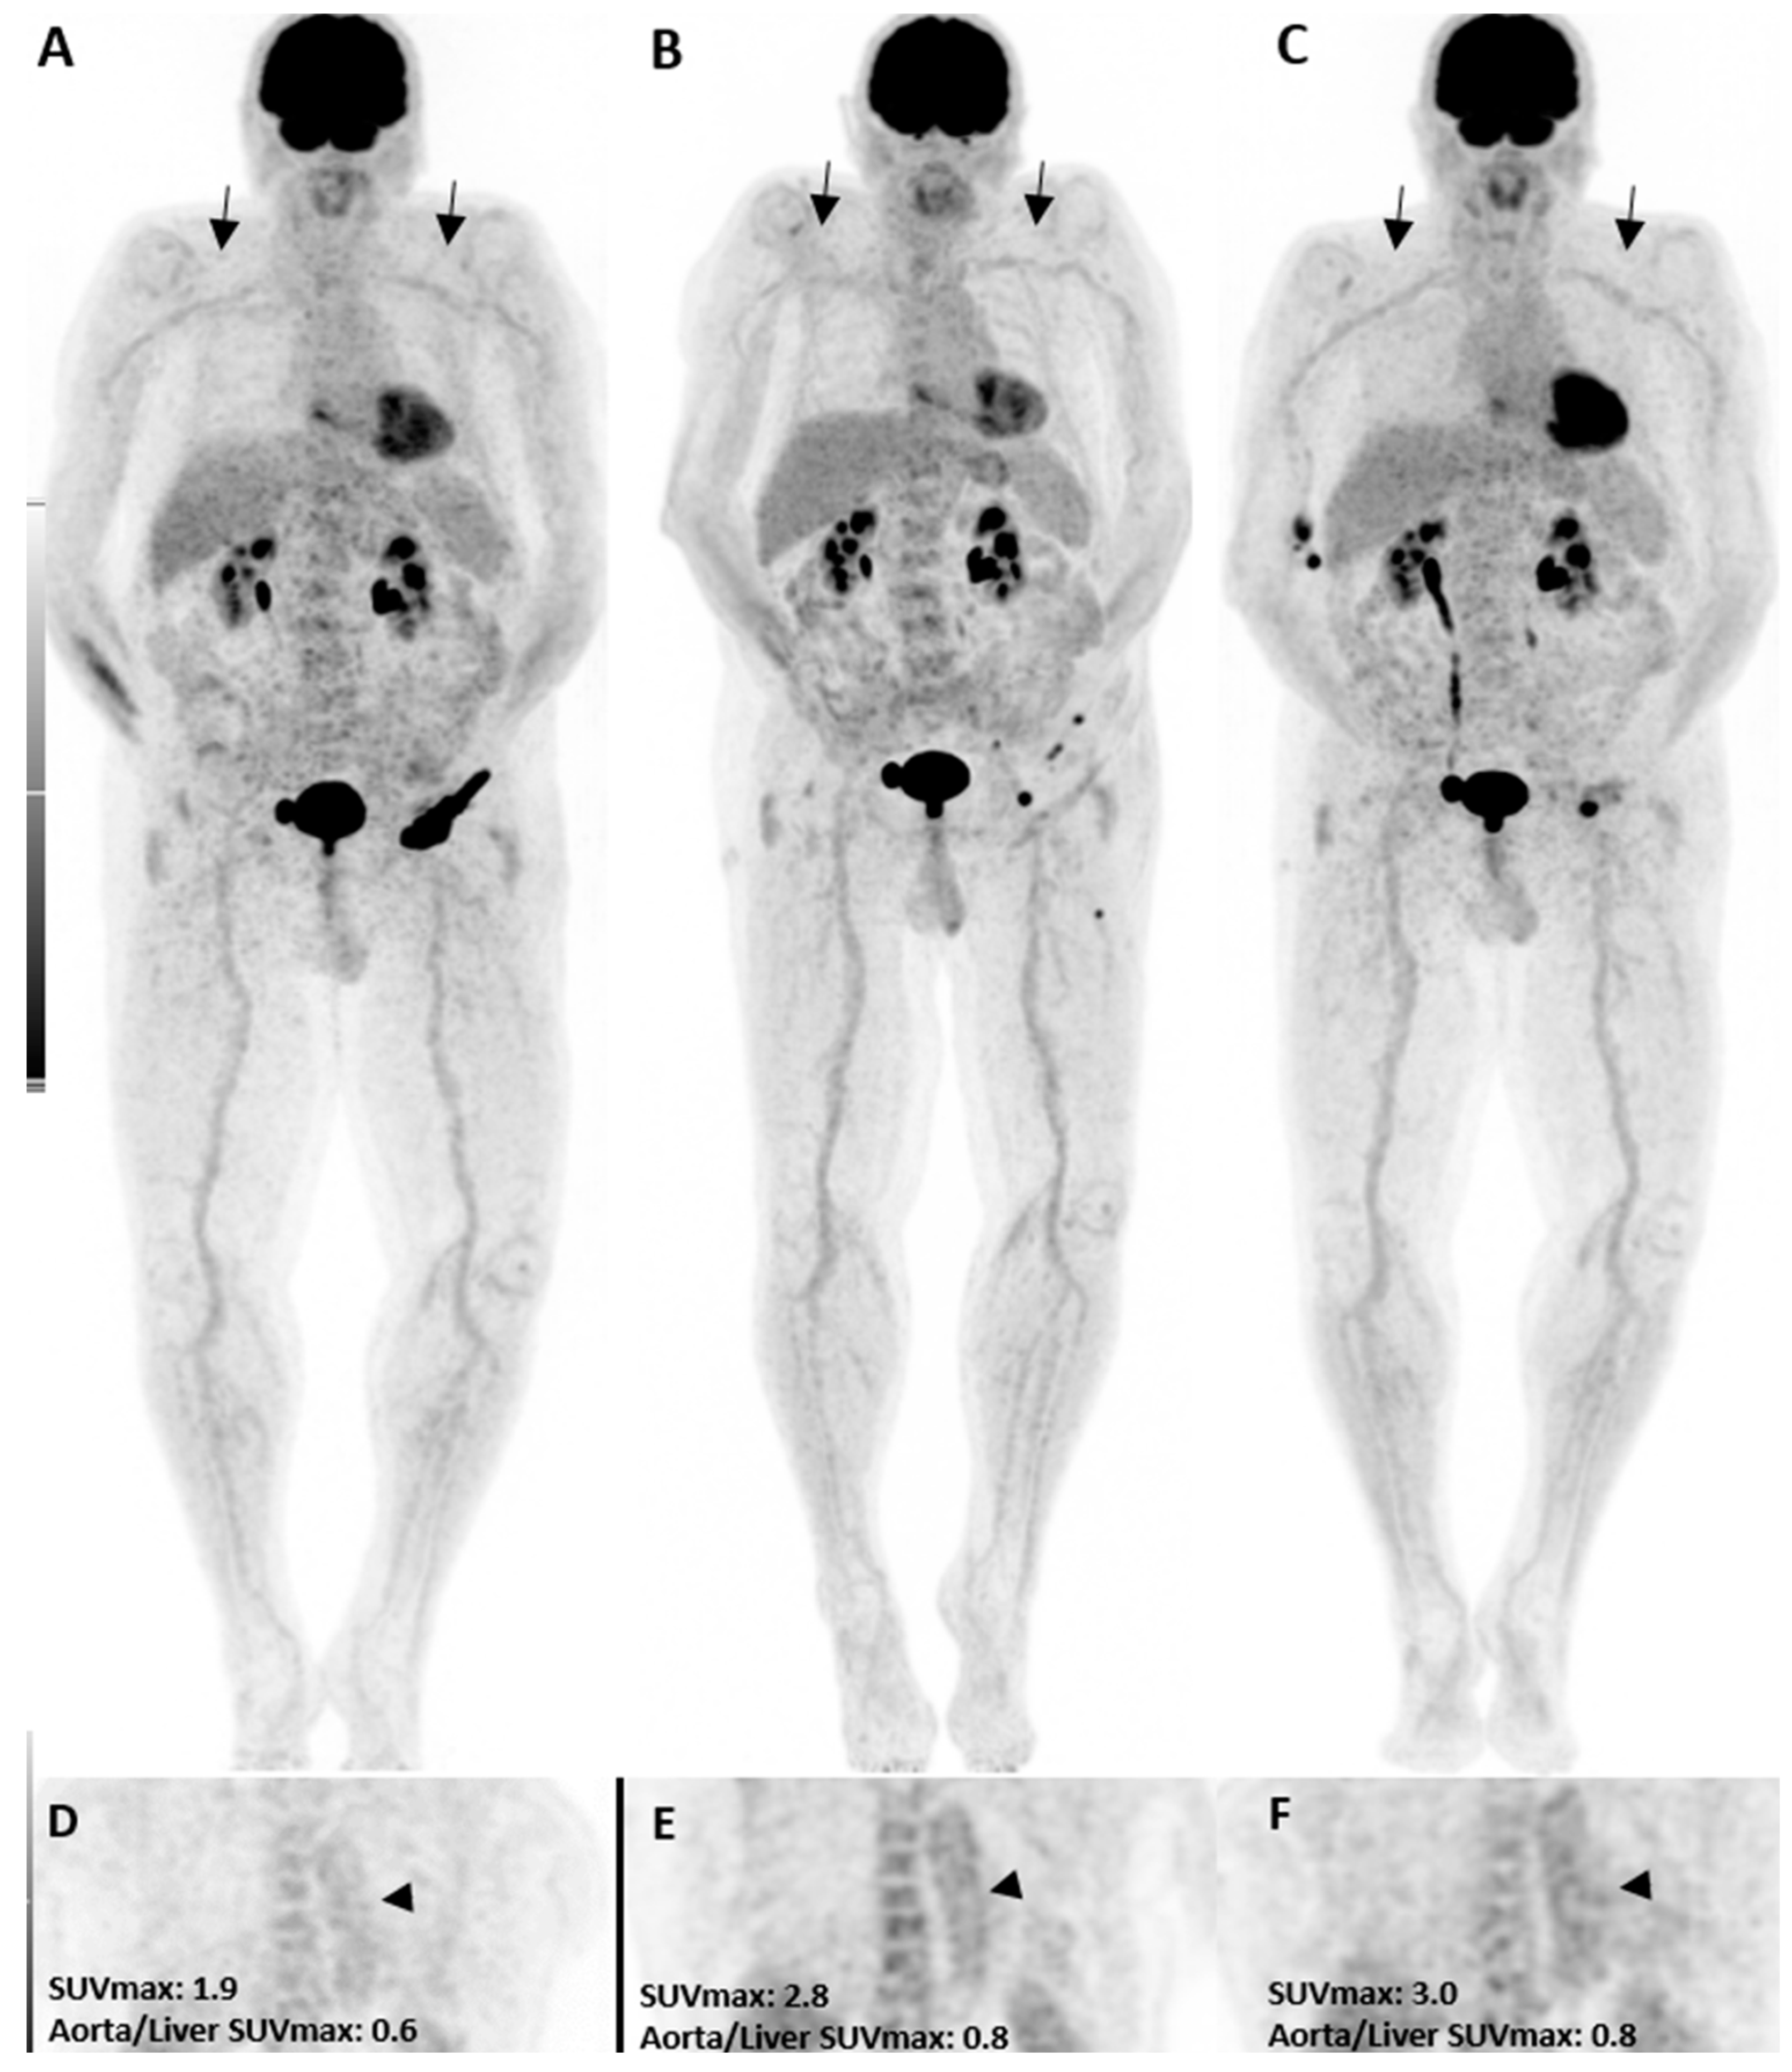

In the pre-treatment [18F]FDG PET/CT, three patients had grade 2 uptake in the thoracic aorta, while only one had a grade 2 uptake in the abdominal aorta and subclavian artery. Three months after treatment, grade 2 uptake was increased in all vascular territories (Figure 1). The thoracic aorta showed the highest amount of grade 2 uptake in our study in all [18F]FDG PET/CT images and was considered for statistical analysis. While only three patients had a grade 2 uptake in the initial [18F]FDG PET/CT (PET1), it was increased to five after three months and further increased to twelve patients (seven new cases) six months after immunotherapy. Although the rise was statistically insignificant three months after therapy, it became significant at six months (p-value = 0.01). Interestingly, in those seven new patients with visual presentation of inflammation in the third scan, five presented with other irAEs in the follow-up, including colitis, neuritis, hypophysitis, pneumonitis, and bullous pemphigoid, resulting in therapy termination. One patient discontinued therapy due to a personal request. Moreover, three of those five patients with grade 2 uptake in both PET2 and PET3 showed early disease progression thereafter, and the treatment was discontinued.

Figure 1.

A patient with the diagnosis of melanoma with ongoing immune checkpoint inhibitors treatment without a history of cardiovascular diseases or clinical evidence of vasculitis. [18F]FDG PET/CT maximum intensity projections (B,C), as well as coronal (E,F) views, three and six months after treatment initiation, are shown. The mild increase in uptake intensity of the aorta and subclavian arterial walls was visually seen compared to the pretreatment (A,D, arrows) images. Semi-quantitative analyses by SUVmax were correlated with visual findings showing a mild increasing pattern of [18F]FDG uptake suggestive of immunotherapy-related mild arterial wall inflammation.

Table 2 shows the mean value of the thoracic aorta SUVmax, SUVmean of the venous blood pool, and SUVmax over the liver and the calculated ratios before treatment and three and six months later. The absolute values of SUVmax and SUVmean were not different between the three groups. However, the ratio of thoracic aorta SUVmax to liver SUVmax was significantly higher in PET2 and PET3 compared to PET1 (p-value = 0.01). Further post hoc analysis revealed that the ratio was not significantly different between PET2 and PET3 (p-value = 0.43). The same data were depicted in Table 3 and Table 4 for the subclavian artery and abdominal aorta, respectively. In a similar pattern to the thoracic aorta, the vessel-to-liver SUVmax ratio was significantly higher in PET2 than PET1 for the subclavian artery (p-value = 0.01). However, this significant trend could not be seen for the abdominal aorta. There was no other significant difference between the three PET series regarding SUVmax, SUVmean, and target-to-background ratios.